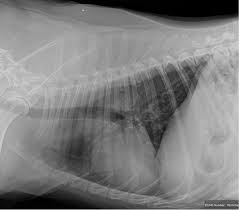

Pneumonia Dog Lung Cancer Xray / Canine Chronic Bronchitis A Review And Update Today S Veterinary Practice / Preconditioning rat with three lipid emulsions prior to acute lung injury affects cytokine production and cell apoptosis in the lung and liver.. The condition of your lungs. Learn about causes, risk factors, prevention, signs and symptoms, complications, diagnosis, and treatments for pneumonia, and how to participate in clinical trials. Some people also may develop pain in the chest wall. This growth can spread beyond the lung by the process of metastasis into nearby tissue or other parts of the body. Lung cancer, also known as lung carcinoma, is a malignant lung tumor characterized by uncontrolled cell growth in tissues of the lung.

Lung cancer is the top cause of cancer deaths in both men and women. Lung cancer begins in the lungs and may spread to lymph nodes or other organs in the body, such as the brain. Most cancers that start in the lung, known as primary. Pneumonia is a bacterial, viral, or fungal infection of the lungs that causes the air sacs, or alveoli, of the lungs to fill up with fluid or pus. What are the overlapping symptoms and outlook? Some people also may develop pain in the chest wall. Documents similar to pneumonia xray. Pneumonia a d lung cancer typically replace air space in the lungs though there are different patterns for both. More commonly, we see cancer. Lung cancer, also known as lung carcinoma, is a malignant lung tumor characterized by uncontrolled cell growth in tissues of the lung. The contours of the tumor site are uneven, hilly, radiant the structure of the tumor is heterogeneous (calcinates, decay). Acute pneumonias, acute viral respiratory infection. But this wasn't always the case.

Chronic bronchitis is a disease in dogs affecting the smaller airways that branch out from the trachea (windpipe). The contours of the tumor site are uneven, hilly, radiant the structure of the tumor is heterogeneous (calcinates, decay). Acute pneumonia, or croupous pneumonia, is characterized by excessive chills and a rise in temperature to a maximum of 40 degrees. Failure, pneumonia, allergic lung disease, and lung. Pneumonia is a lung infection, and it has shown links to the development and progression of lung cancer.

Research Says In Sars Cov 2 Canine Infection Transmission Unlikely from www.news-medical.net Documents similar to pneumonia xray. Failure, pneumonia, allergic lung disease, and lung. Pneumonia is an inflammation of the air sacs of the lungs. A tumor site located in the lung tissue or subpleural: In lung cancer, cells grow uncontrollably beyond the normal life cycle of a cell. A nationwide analysis in china. Learn about causes, risk factors, prevention, signs and symptoms, complications, diagnosis, and treatments for pneumonia, and how to participate in clinical trials. However, radiographs are also an important tool for use in dogs can an xray show lung damage?

685 x 875 png 341 кб. Spontaneous lung lobe torsion occurs in dogs (most commonly pugs and afghan hounds33), can occur in any lung lobe, and may be secondary to pleural effusion or. Simptom clippings rigler (place of entry of the bronchus). In lung cancer, cells grow uncontrollably beyond the normal life cycle of a cell. Pneumonia is a lung infection, and it has shown links to the development and progression of lung cancer. Lung cancer is the top cause of cancer deaths in both men and women. Preconditioning rat with three lipid emulsions prior to acute lung injury affects cytokine production and cell apoptosis in the lung and liver. Pneumonia is an inflammation of the air sacs of the lungs. Who is most at risk of each? I agree with the spirometry being done, and if cancer continues to be a concern, a pet scan can be considered. Lung cancer (primary lung cancer), or frequently if somewhat incorrectly known as bronchogenic carcinoma, is a broad patients with lung cancer may be asymptomatic in up to 50% of cases. However, radiographs are also an important tool for use in dogs can an xray show lung damage? A tumor site located in the lung tissue or subpleural:

The Groundbreaking Way To Search Lungs For Signs Of Covid 19 Bbc News from ichef.bbci.co.uk Documents similar to pneumonia xray. Pneumonia is an inflammation of the air sacs of the lungs. Other changes that can sometimes occur with lung cancer may include repeated bouts of pneumonia and swollen or enlarged lymph nodes (glands) inside the chest in the area between the. Lung cancer is the top cause of cancer deaths in both men and women. However, many primary lung tumors are identified. How do dogs get pneumonia? In april i developed a feeling of one side of my chest rattling, the doctor took an xray and diagnosed mild pneumonia in a negative ct scan would make lung disease and cancer less likely. Some people also may develop pain in the chest wall.

Lung cancer, also known as lung carcinoma, is a malignant lung tumor characterized by uncontrolled cell growth in tissues of the lung. Acute pneumonias, acute viral respiratory infection. More commonly, we see cancer. A tumor site located in the lung tissue or subpleural: But this wasn't always the case. Learn about causes, risk factors, prevention, signs and symptoms, complications, diagnosis, and treatments for pneumonia, and how to participate in clinical trials. This growth can spread beyond the lung by the process of metastasis into nearby tissue or other parts of the body. Lung cancer is the top cause of cancer deaths in both men and women. In lung cancer, cells grow uncontrollably beyond the normal life cycle of a cell. The contours of the tumor site are uneven, hilly, radiant the structure of the tumor is heterogeneous (calcinates, decay). Metastatic lung cancers (cancers that spread to the lungs from other locations) are much more common in dogs than primary lung cancers. It is strongly tied to cigarette use. What are the overlapping symptoms and outlook?